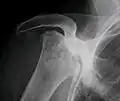

Front X-ray of right knee of an adolescent (epiphyseal plates are open): arrows point to avascular necrosis and developing osteochondritis dissecans in the outer medial condyle of femur

In the early stages, bone scintigraphy and MRI are the preferred diagnostic tools.[18][19]

X-ray images of avascular necrosis in the early stages usually appear normal. In later stages it appears relatively more radio-opaque due to the nearby living bone becoming resorbed secondary to reactive hyperemia.[2] The necrotic bone itself does not show increased radiographic opacity, as dead bone cannot undergo bone resorption which is carried out by living osteoclasts.[2] Late radiographic signs also include a radiolucency area following the collapse of subchondral bone (crescent sign) and ringed regions of radiodensity resulting from saponification and calcification of marrow fat following medullary infarcts.